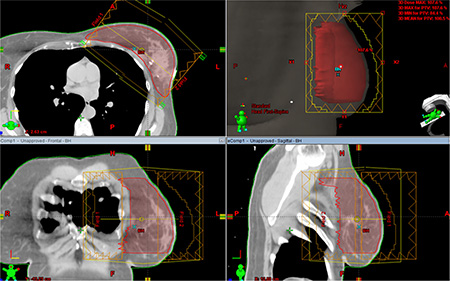

eComp plans used the identical beam arrangements as the corresponding 3DCRT plans. Instead of using wedges, the tissue compensation function was employed to create a dynamic MLC fluence map. The fluence map was edited manually to achieve a desired dose distribution. Then, the optimum fluence map was extended beyond the patient surface by the skin flash tool provided in Eclipse then converted to a deliverable fluence based on the specific characterization of the dynamic MLC (Figure 7).

Figure 7: Electronic tissue compensation was employed to create a dynamic MLC fluence map. The optimum fluence map was extended beyond the patient surface by the skin flash tool provided in Eclipse then converted to a deliverable fluence based on the specific characterization of the dynamic MLC.